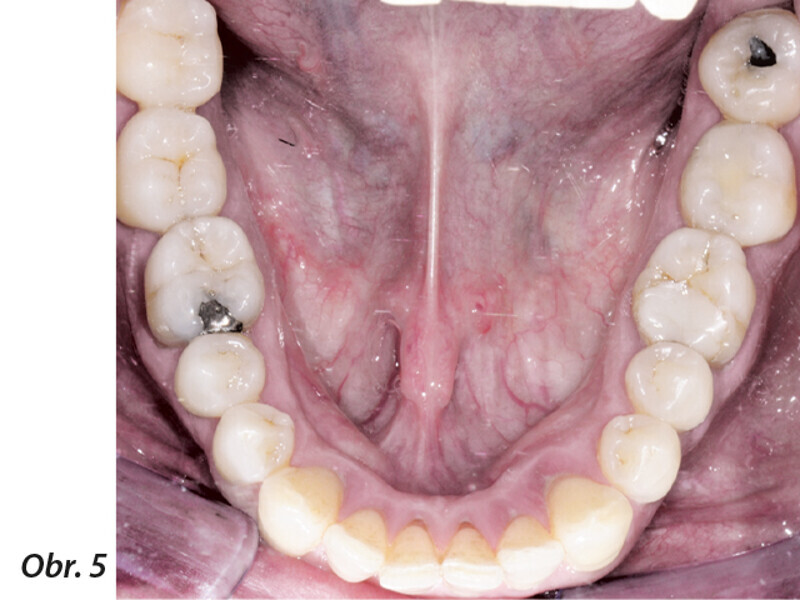

Multidisciplinární léčba u pacienta se závažnou parodontitidou